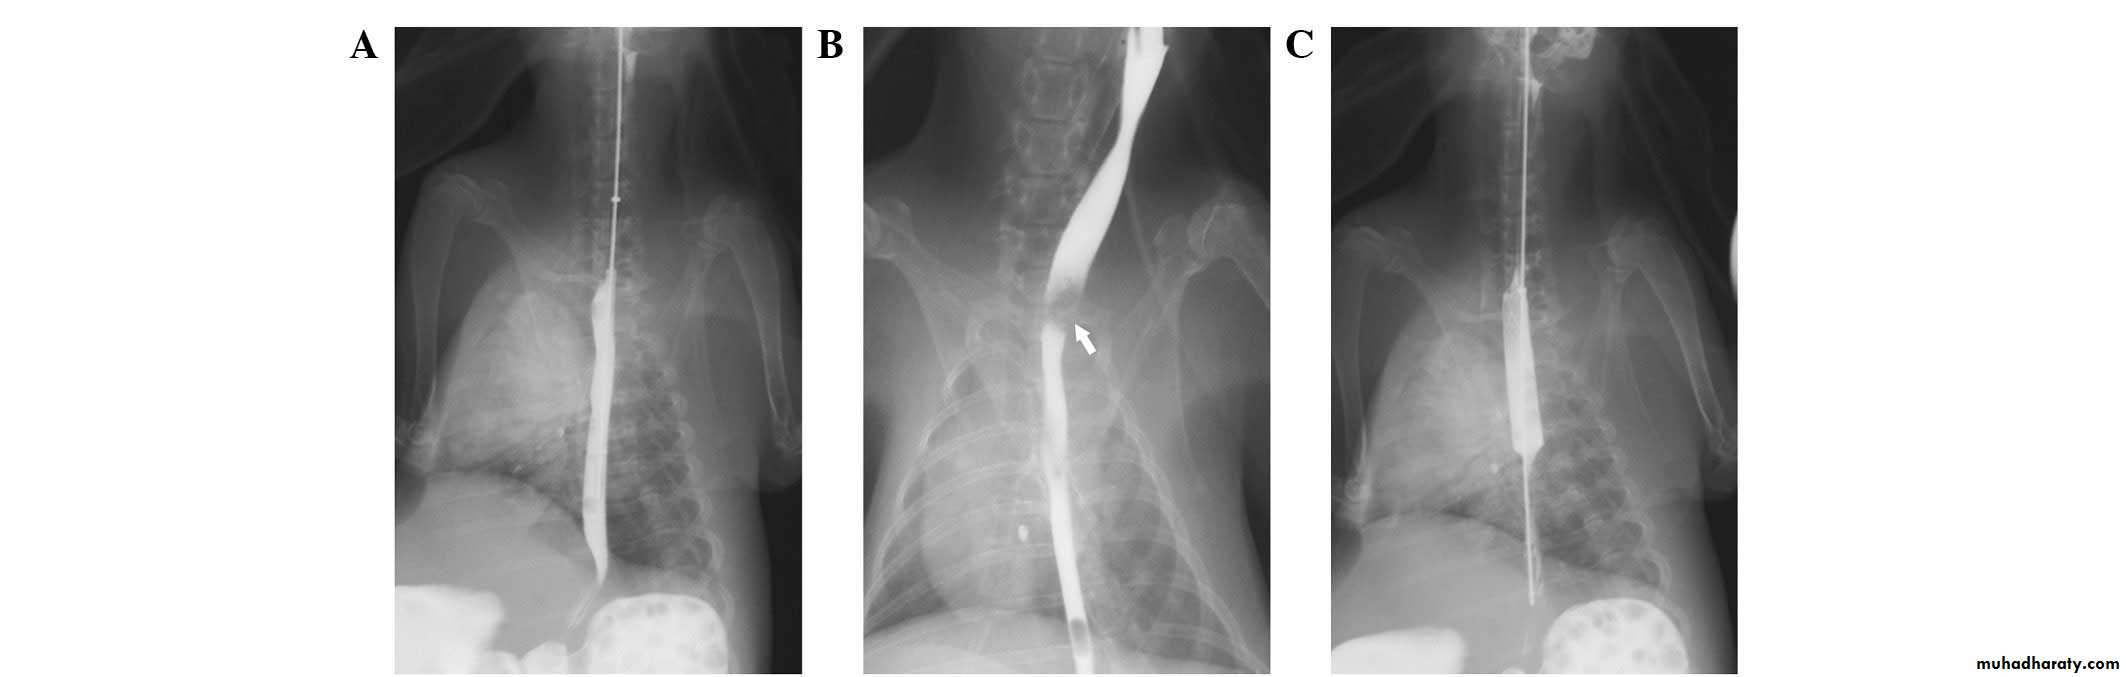

Chest x-ray may be abnormal in late dis., with widening of mediastinum (oesophageal dilatation) and presence of aspiration pneumonitis.Barium swallows . Tapered narrowing (bird beak) of the lower oesophagus and dilating body of oesophagus, a peristaltic and food filled (sigmoid oesophagus).